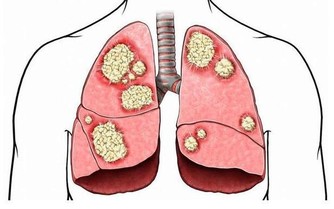

大腸癌的遠處轉移主要有兩種方式:淋巴轉移和血行轉移。

腫瘤細胞通過淋巴管轉移至淋巴結,也可通過血行轉移至肝臟、肺部、骨等部位。